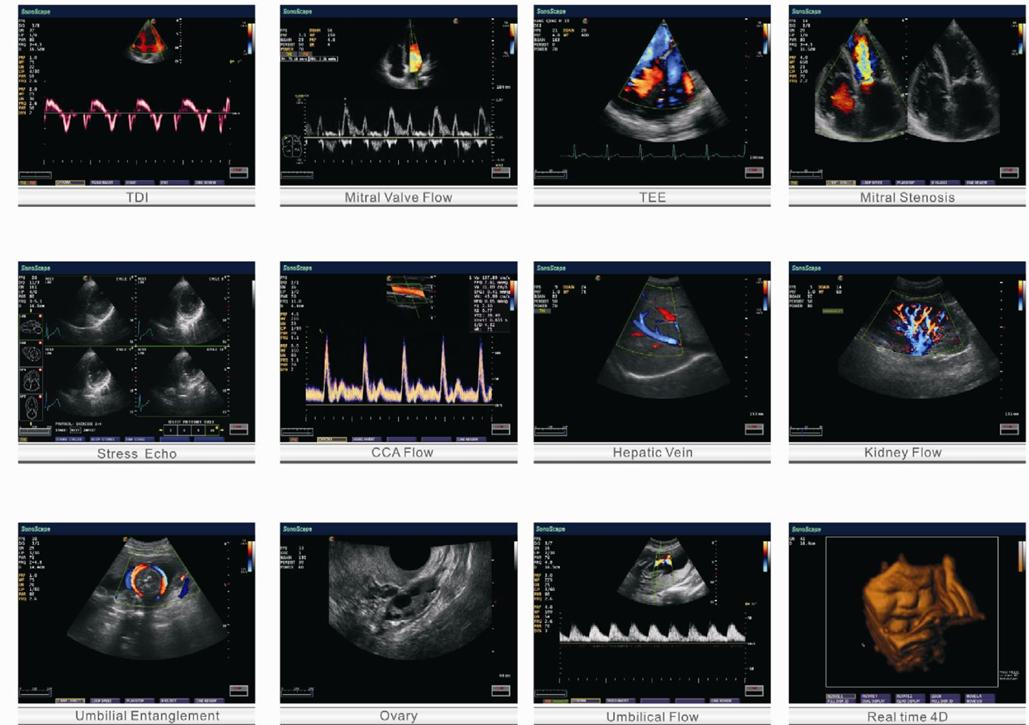

- Doppler mô & Doppler màu: Hình ảnh huyết động chi tiết, hỗ trợ tốt trong tim mạch và mạch máu.

- 3D/4D Imaging: Phục vụ sản – phụ khoa, mang đến hình ảnh thai nhi trực quan, sống động.

- Chế Độ Chụp Ảnh: Đa dạng các chế độ hình ảnh bao gồm B, 2B, 4B, M, THI, CFM, PDI, DirPDI, PW, và HPRF, cho phép chụp ảnh đa chiều.

4. Ứng dụng trong siêu âm chẩn đoán bệnh:

- Small Parts (tuyến giáp, ngực, những phần nông,…)

- Bụng (gan, lách, thận, tuyến tụy)

- Mạch máu (động mạch cảnh, ngoại vi tàu)

- Tim mạch

- Sản khoa (tử cung, phần phụ, thai nhi)

- Phụ khoa

- Tiết niệu

- Cơ xương khớp

- Craniocerebral

- Cấp cứu (tùy chọn)

- ICU (tùy chọn)